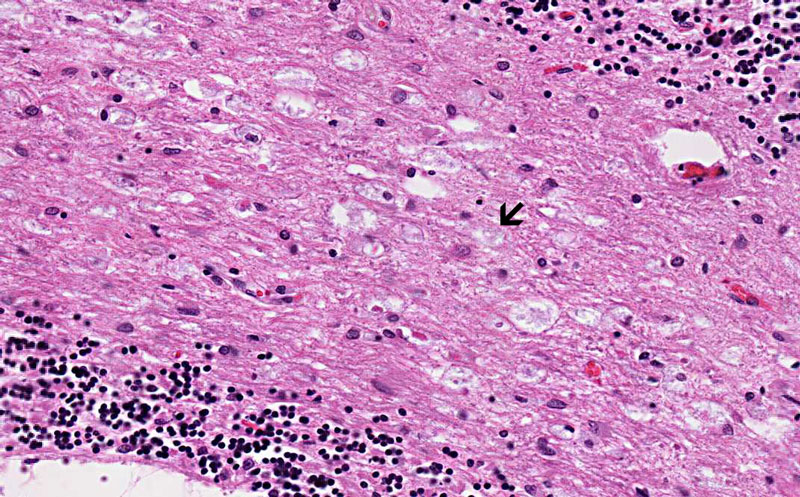

Luxol Bast Blue-Cresyl Violet

Loss of myelin: Myelin is staind blue in Luxol fast blue-Cresyl violet preparation. This image is taken from the cerebral cortex and subcortical white matter from a different case of x-linked adrenoleukodystrophy. Note that there is extensive loss of myelin in the deeper part of the subcortical white matter (scw). Myelin in the subcortical fibers are preserved.